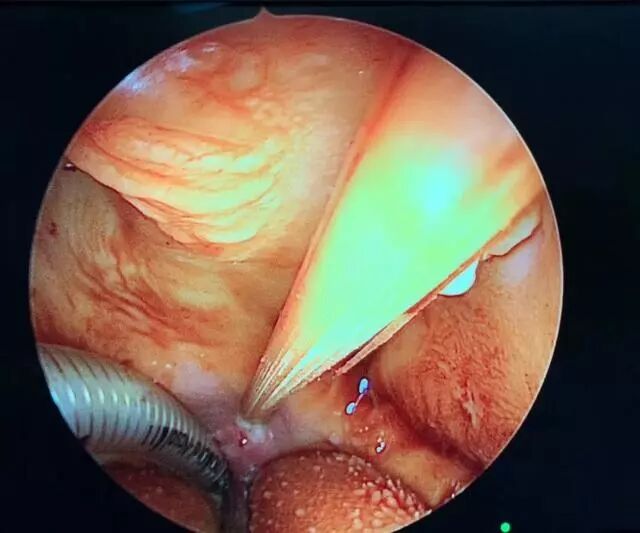

無影燈下,姜彥及團(tuán)隊成員將患兒口咽部充分暴露后,將其左側(cè)咽部及周邊軟組織輕輕切開,直至患兒的顱底和上頸椎部位。

△內(nèi)鏡顯示的手術(shù)過程

在利用先進(jìn)的磁導(dǎo)航系統(tǒng)探明損傷位置和血管走向后,姜彥順著異物插入方向,小心翼翼地將竹簽松動并倒退出來,致命的竹簽被成功取出。